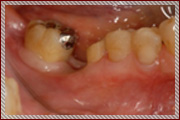

治療前のシミュレーション

施術前のレントゲン

サージガイドを使用することによって計画された位置に正確な施術が可能です